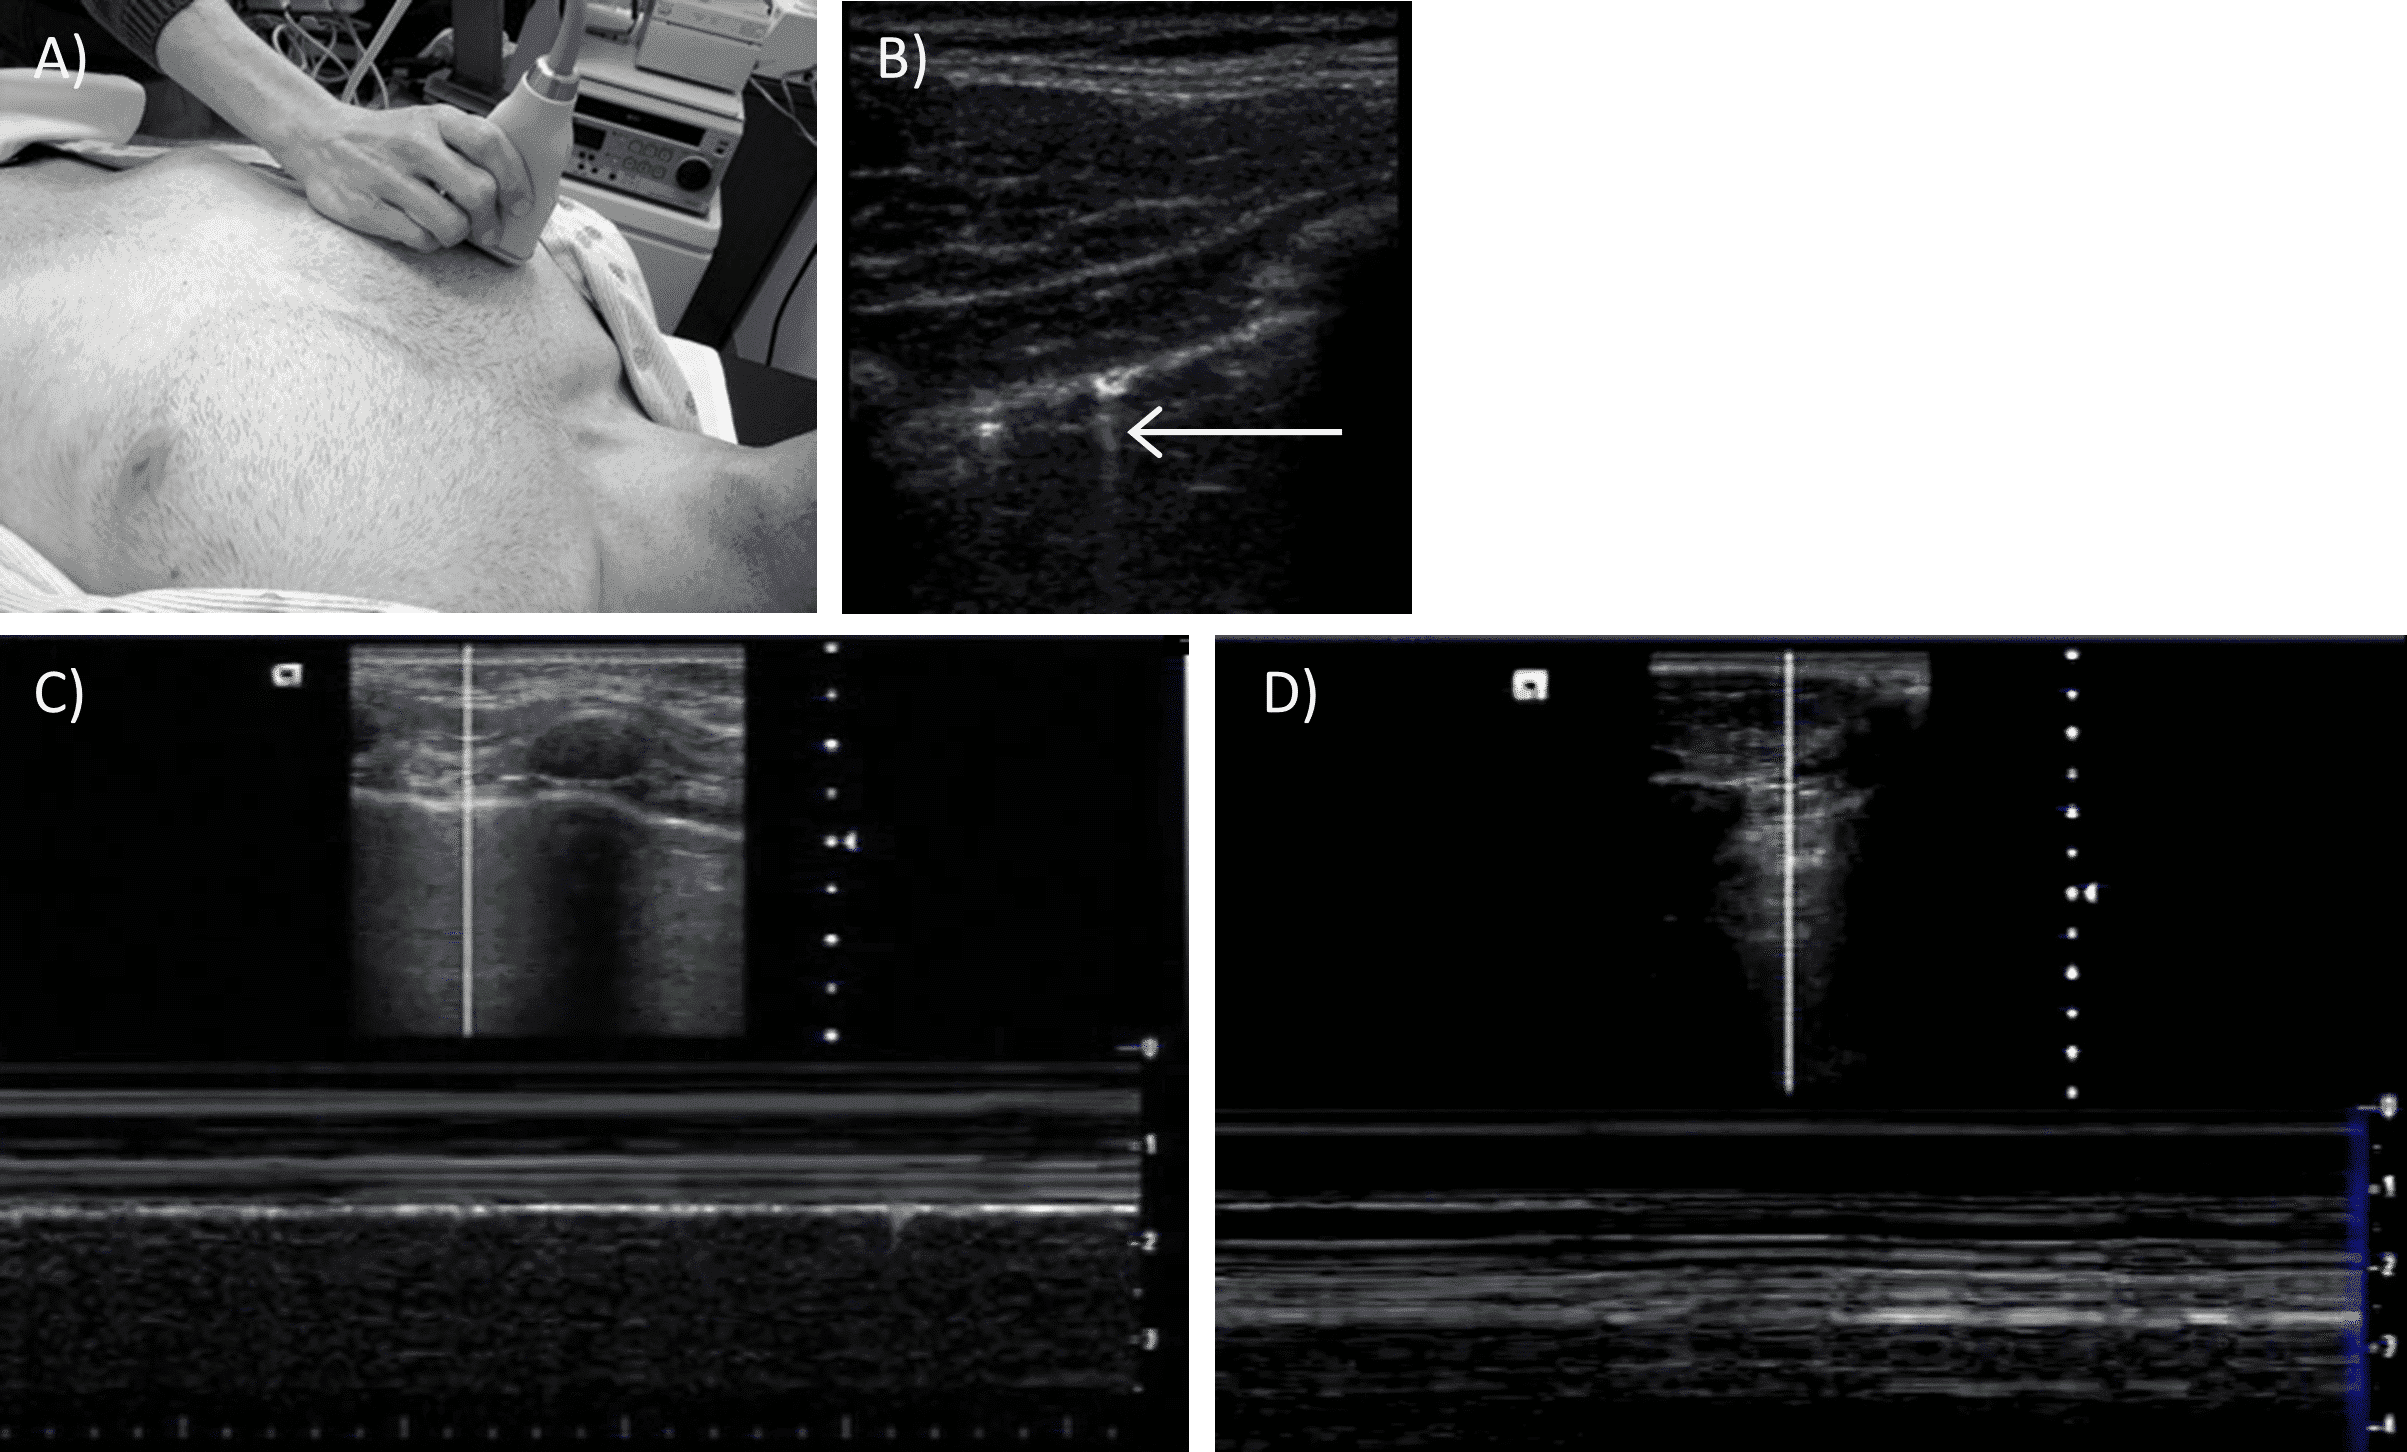

The presence of fluid on any of the views is considered a positive exam. Fluid typically appears as an anechoic collection, although clotted blood may appear echogenic. To qualify as a negative exam, all views must be adequately obtained with no evidence of fluid. If any portion of the exam cannot be adequately assessed, the FAST exam is considered indeterminate. A low frequency (2.5 to 5MHz) curvilinear probe is used for the FAST exam, with the addition of a higher frequency 5 to 10 MHz probe to perform the E-FAST exam (Figure 1).

A) 5-10 MHz probe

B)

2.5-5 MHz curvilinear probe

To evaluate for pneumothorax a higher frequency linear transducer (5-10 MHz) is typically used. To evaluate for hemothorax the curvilinear probe is more appropriate. The probe is usually placed in the midclavicular line around the 3rd or 4th intercostal space with the indicator pointed to the patient’s head (Figure 8A). Both the right and left sides of the chest are imaged. To evaluate for pneumothorax,sliding of the visceral and parietal pleura is examined either using gray scale B-mode, M-mode or doppler.

With good inspiratory effort or when a patient is mechanically ventilated with adequate chest expansion, the sliding of the visceral on parietal pleura is easy to visualize and can resemble “ants marching in a line”.  In patients with a pneumothorax, lung sliding will be absent. This view can also be used to evaluate for the presence of “comet tail artifacts”, which are caused by areas of interstitial edema on the visceral pleura and appear as vertical hyperechoic streaks extending from the visceral pleura “downwards”, deep into the lung (Figure 8B).

The presence of comet tails is normal, and these are not present in patients with a pneumothorax. M-mode may also be used to evaluate for pneumothorax. Patients with a normal lung will have a linear pattern above the pleural line and a granular pattern below the pleural line, the so-called “seashore sign” (Figure 8C). Patients with a pneumothorax will have a linear pattern throughout, also referred to as the “barcode sign” (Figure 8D). Hemothorax is most easily evaluated on the flank views at the costophrenic angle.

Pleural view.

A) Probe positioning. B) Comet tail artifact (arrow).

C) M mode view of lung sliding in normal lung (“seashore sign”). D) M mode view of lung sliding in lung with pneumothorax (“barcode sign”).